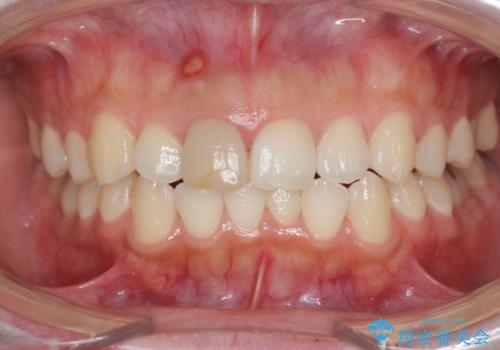

根管治療を行ったことで、歯ぐきのできものは治癒し再発をしなくなりました。

歯ぐきにできものができた 前歯の色調改善